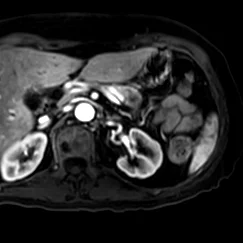

Contrast enhanced MR shows hypoenhancing pancreatic lesion